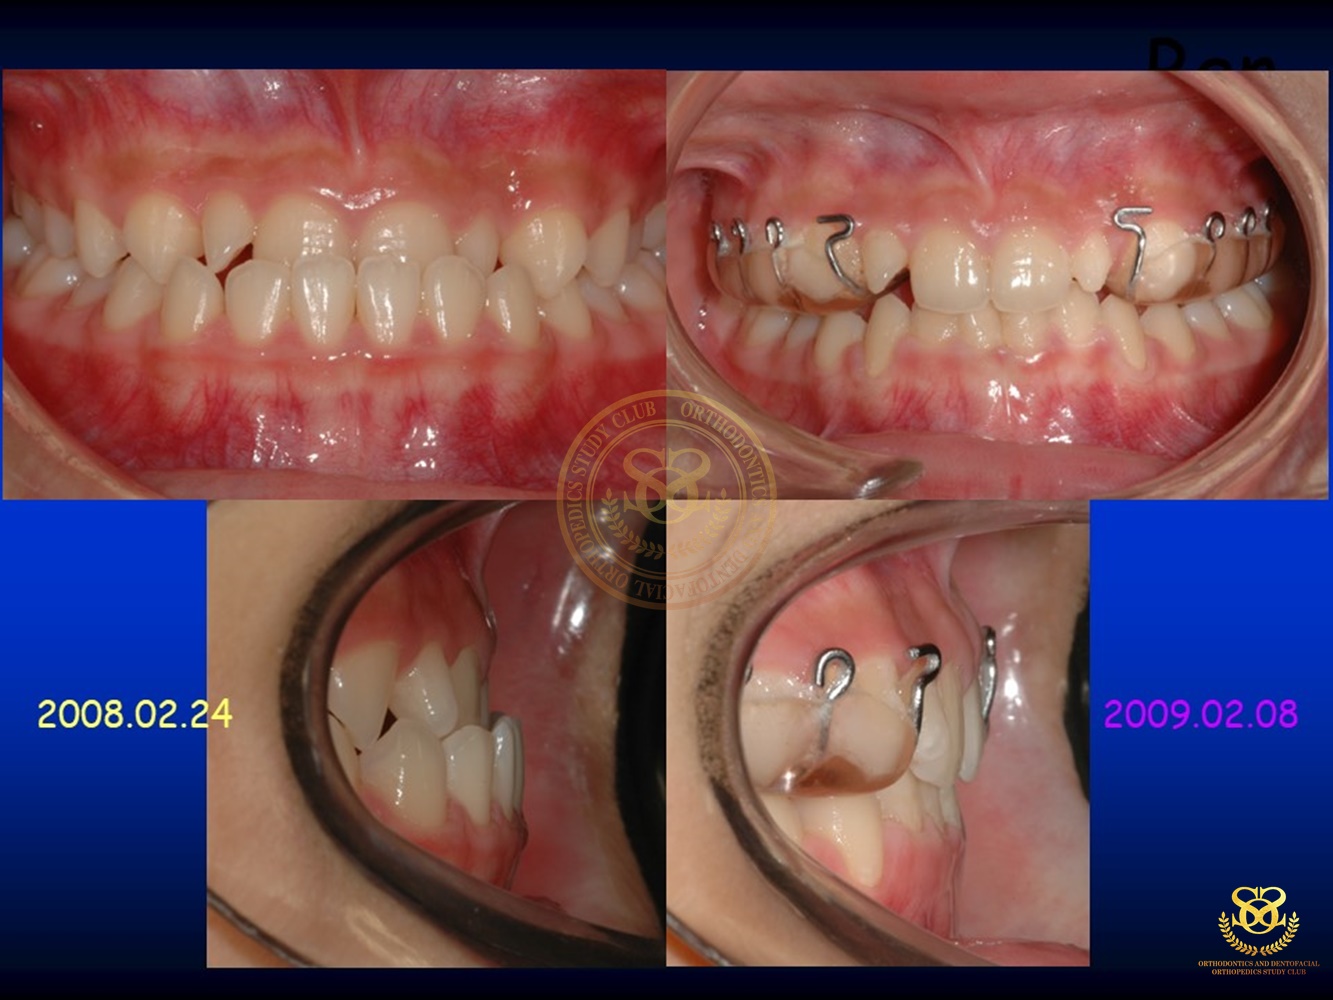

Treatment of Pseudo Class III (Class I Molar Relationship) and management of the embedded maxillary canine (Pt. Miss J.I.)